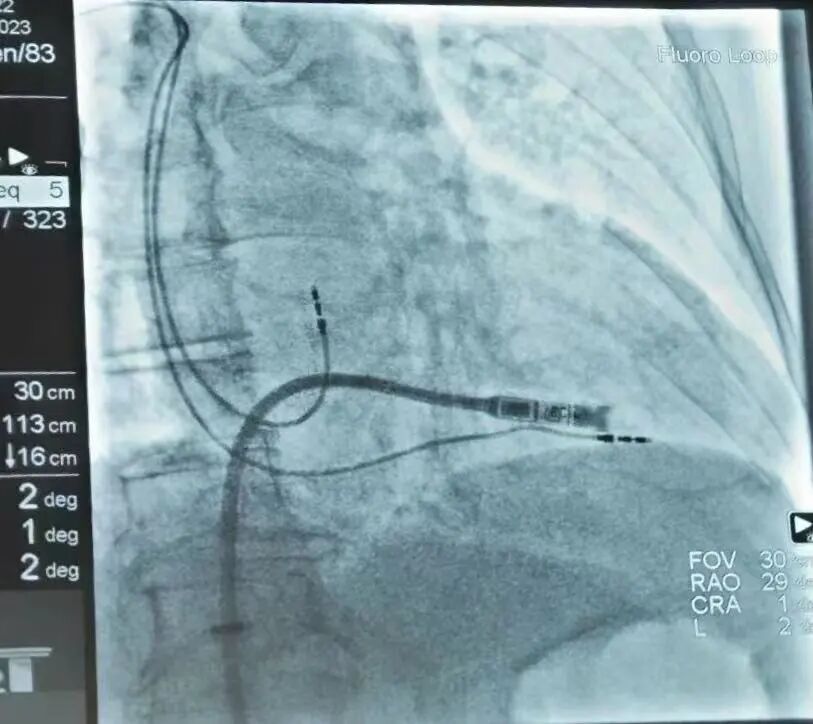

无导线起搏器植入过程

无导线起搏器成功植入

在哈医大二院李述峰老师的指导下,手术在局部麻醉下进行,通过股静脉穿刺,将起搏器通过导管植入到心腔内部,手术时间仅有30分钟,患者术后反应良好,两天后即可恢复正常的工作和生活。